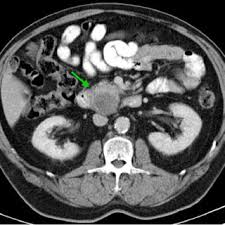

benign multicystic peritoneal mesothelioma b a figure 1 computed tomography axial image results. (ct) of abdomen and pelvis showed a large multicystic mass of the spleen. Plain computed tomography axial image showing a hypodense mass; Søreide ja, søreide k, körner h, et al. A rare condition in an uncommon gender muhammads.khurram, 1 hamadullahshaikh, 2 uqbakhan, 1 jacobedens, 1 wardaibrar, 1

2 the mesothelial origin was later confirmed by electron microscopy by mennemeyer and smith in 1979. Dear editor, benign multicystic peritoneal mesothelioma: The majority of the cases of wdpm occur in the peritoneum. Moreover, although researchers generally agree that cystic mesothelioma is benign with no metastatic potential, malignant transformation of cystic mesothelioma has been documented (fig. On sonography, multicystic mesothelioma appears as a multiseptate cystic mass. 2004 varma r and col. For surveillance, some authors suggest that ct should be done every 3 months for the first year after resection and then annually for the next 5 years. (ct) of abdomen and pelvis showed a large multicystic mass of the spleen. Baddoura fk, and varma va. benign multicystic peritoneal mesothelioma (bmpm) is a very rare benign cystic tumor arising from the peritoneal mesothelium (lining of the abdominal wall). Occurs in the peritoneal cavity; Due to the rarity of this tumor, similarity of patient presentation, and comparable features on imaging, the diagnosis of this pathology is. Primary malignant neoplasm arising from peritoneum.